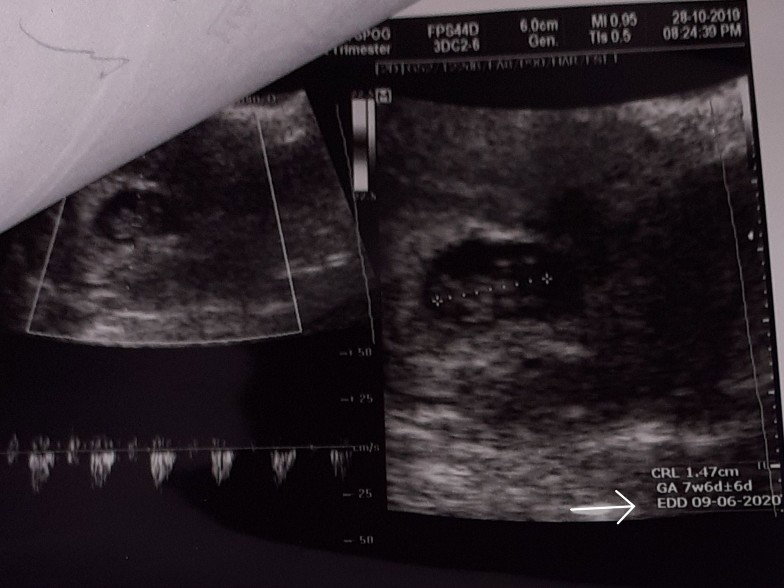

edd 09.06.2020

Bunda ada yg tau gak....tulisan edd 09.06.2020 dipojokan poto usg.itu HPL bukan ya...lupa gk sempet nanya k dokternya.